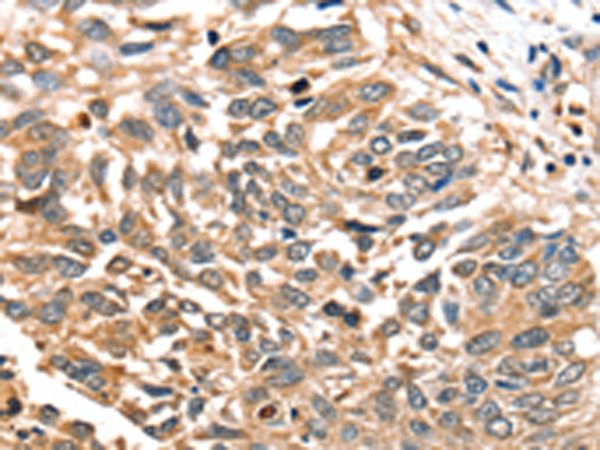

分类: 科研抗体货号: P12165别名: hSiah2应用: IHC反应种属: Human, Mouse, Rat